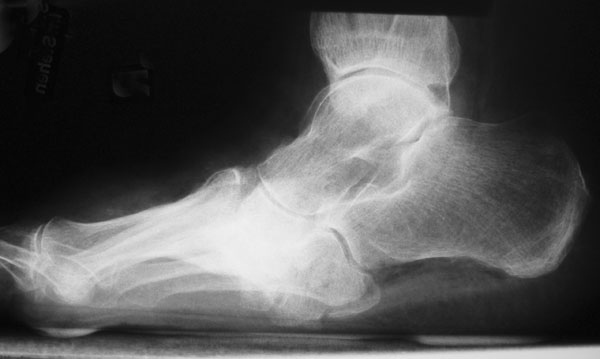

Die Nativröntgenuntersuchung der Füße erfolgt beim DFS standardisiert durch folgende Projektionen: beide Vorfüße dorso-plantar im Stehen (evtl. im Schuh), beide Füße mit OSG seitlich im Stehen, Fußwurzel beidseits 45° schräg, OSG beidseits anterior-posterior. Bei Verdacht auf eine beginnende Osteoarthropathie oder zur Differenzierung zwischen Osteoarthropathie und tiefer Knochen-/Weichteilinfektion kann die Durchführung einer MR-Tomographie und ggf. 3-Phasen-Skelett-Szintigraphie von Nutzen sein 22. Bei Achsfehlstellungen im Rückfuß wird zusätzlich die Saltzman-Aufnahme durchgeführt. Insbesondere zur Planung rekonstruktiver Eingriffe bei Osteoarthropathie ist eine Computertomographie mit 3-D-Rekonstruktion oft hilfreich (siehe Kapitel Radiologische Diagnostik). Eine laborchemische Untersuchung der humoralen Entzündungsparameter (Blutbild, BKS, quantitatives C-reaktives Protein) ist bei Verdacht auf eine Infektion und zur Abgrenzung zu einer DNOAP obligat. Lokale Druckspitzen lassen sich mit Hilfe der Pedobarographie identifizieren 26.